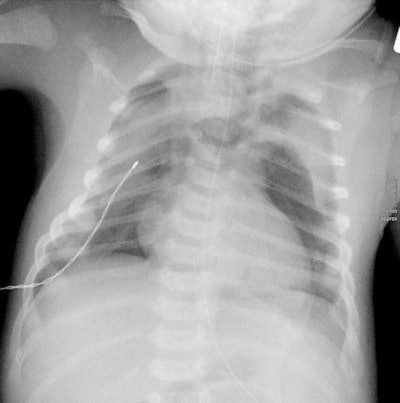

Full-term newborn after cesarean section with pneumomediastinum and pneumothorax on both sides. Image courtesy of Dr. Gabriele Hahn.How would you like to see pediatric radiology develop in Germany?

A real clinical feel for the work, coupled with a "radiological eye." Pediatric radiologists need a thorough knowledge of childhood disorders because these differ widely from their adult counterparts. Furthermore, when dealing with children it is a fundamental necessity that practitioners give greater thought to radiation doses, because children are far more sensitive to radiation than adult patients are. Their tissue is still growing and there are also matters of reproduction to consider, so a particularly close watch needs to be kept, to ensure that the smallest possible amounts of radiation are used. This means using caution and having a reliable indication before opting for x-ray and CT scanning for investigations.